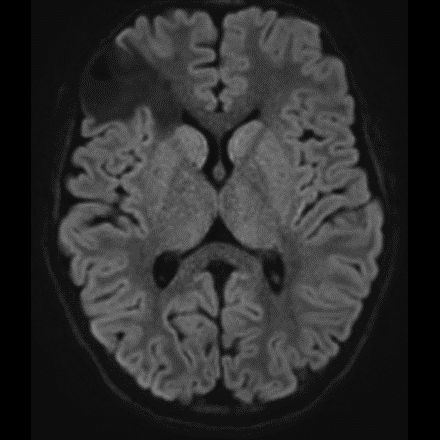

DNET:Özellikle erkek çocuk ve nöbet öyküsüyle gelen hasta kortikal yerleşim ve t1 ağırlıklı serilerde hipointens t2a ve flair serilerde ise hiperintens görülmesi bu tanıma uymaktadır. Hastaların 5’te birinde frontal lobda da tutulum olabilir. Lezyon çevresinde ödem ya da içerisinde kalsifik odak izlenmemiştir:

DNET:Özellikle erkek çocuk ve nöbet öyküsüyle gelen hasta kortikal yerleşim ve t1 ağırlıklı serilerde hipointens t2a ve flair serilerde ise hiperintens görülmesi bu tanıma uymaktadır. Hastaların 5’te birinde frontal lobda da tutulum olabilir. Lezyon çevresinde ödem ya da içerisinde kalsifik odak izlenmemiştir.